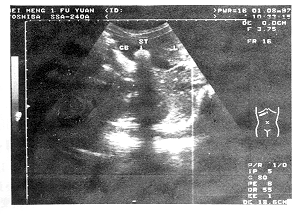

B超诊断5岁幼儿胆囊结石一例 患儿, 女, 5岁, 曾因反复上腹部疼痛被当地医院以“胃病”治疗, 效果不佳。 近日又因上腹部疼痛、 恶心、 食欲减退来我院就诊。 查体: 皮肤、 巩膜无黄染, 心、 肺(-), 右上腹压痛(+), 体温37.2℃。 B超所见: 患儿胆囊46 mm×15 mm, 前壁厚2.1 mm, 稍毛糙。 于胆囊内见14 mm×10 mm的强回声团, 后伴声影, 可随体位改变而移动(附图)。 胆总管内径3 mm, 回声正常。 B超诊断: 胆囊结石(单发); 慢性胆囊炎。 后经手术证实。

GB: 胆囊, ST: 结石, L: 肝脏

附 图 幼儿胆结石